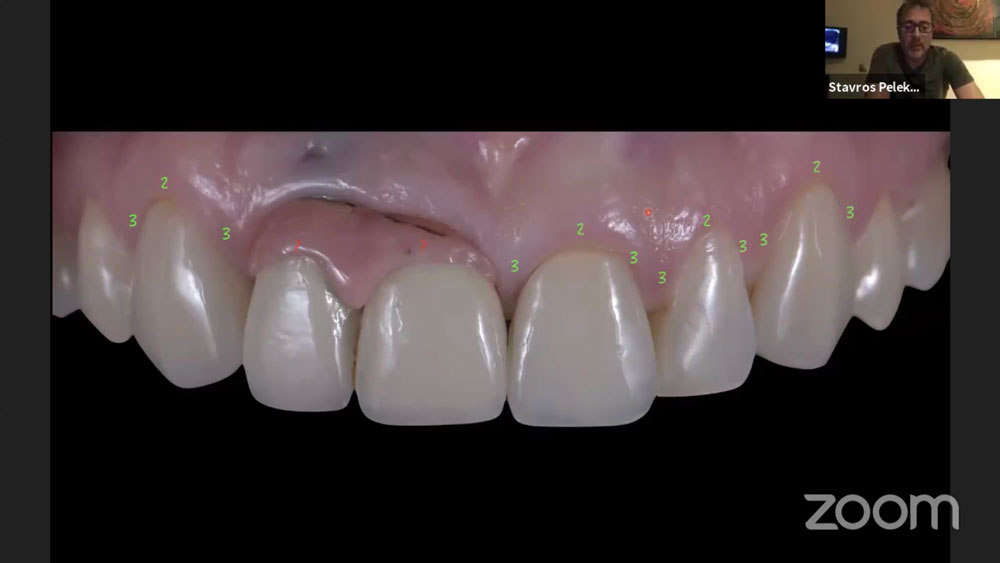

Το κλινικό περιστατικό που παρουσίασε στις 14 Απριλίου ο προσθετολόγος Σταύρος Πελεκάνος αφορούσε γυναίκα 37 ετών, υγιή, μη καπνίστρια και με καλή στοματική υγιεινή, χωρίς περιοδοντικό πρόβλημα. Η ασθενής προσήλθε στο ιατρείο χωρίς να νιώθει πόνο για να βελτιώσει την αισθητική της εικόνα. Είχε δύο εμφυτεύματα στην #11 και #12 που τοποθετήθηκαν δώδεκα χρόνια πριν.

Όλα τα στάδια που ακολουθήθηκαν στα περιστατικά παρουσιάστηκαν βήμα-βήμα μέσα από φωτογραφίες. Η διάδραση μεταξύ των ομιλητών και του κοινού